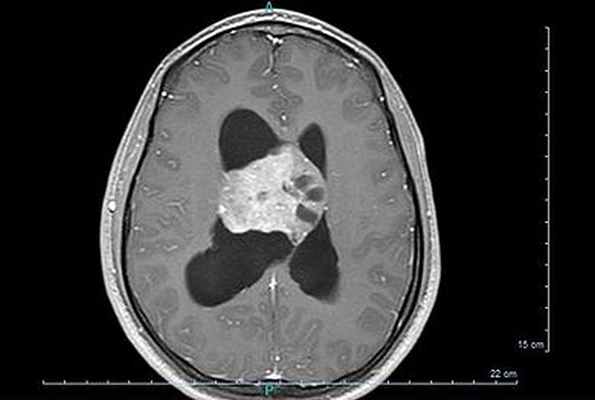

При магнитно-резонансной томографии головного мозга выявлено объемное кистозно-солидное образование с четкими неровными контурами, размерами 5,8 х 7,2 х 4,9 см (5,0 х 4,4 см — приблизительные размеры солидной части) в медиобазальных отделах левой лобной доли, без перифокального отека. Данное образование компри-мирует передние рога боковых желудочков, смещая срединные структуры вправо до 0,5—0,6 см.

МРТ головного мозга, коронарный срез, последовательность повреждений Т1, большая нейроцитома правого бокового желудочка.

Диагноз ставится с помощью визуализации головного мозга, компьютерной томографии или, в лучшем случае, МРТ головного мозга, обнаруживая это гетерогенное образование с тремя основными компонентами (ткань +/- кистозный и кальций) с частичным усилением при введении контрастного вещества.